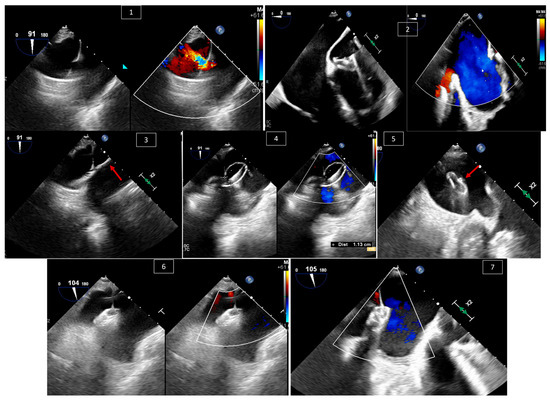

Highlights of Transesophageal Echocardiography During

Highlights of Transesophageal Echocardiography During